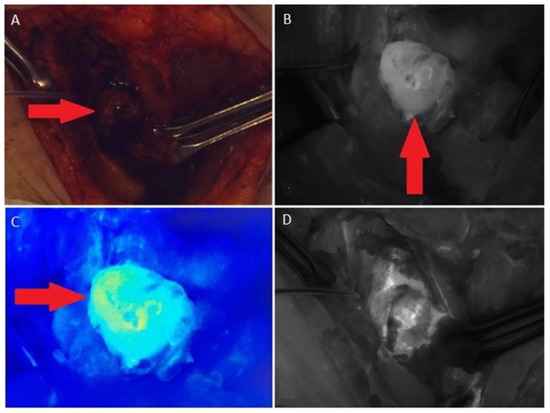

- Single-channel gamma probe Gamma Finder2. The navigational activity of 99mTc-MIBI (150–300 MBq) is administered intravenously 60–90 min before surgery. The detection parathyroid tissue was performed, focusing on the data of preoperative topical diagnostics (ultrasound, CT, planar scintigraphy, SPECT/CT). The gamma probe is used for differential diagnosis of the neck tumors and confirmation of the complete tumor removal.

- Fluorescent angiography system SPY 3000, Novodaq. Intraoperatively, 3–4 mL of the vial with ICG was administered to the patient intravenously, followed by the injection of 10 mL 0.9% NaCl 30–60. ICG appears directly in the tissues; the detecting device must be kept at a distance of 5–20 cm from the area of interest.

| 2018–2019 | Ultrasound: ‘multiple hypoechoic lesions with dimensions of 12 × 7 mm, 9 × 6 mm, 11 × 6 mm and 9 × 5 mm of the left lobe; 1.4 cm lower a new lesion 0.6 cm in diameter’ 99mTc-MIBI scintigraphy with SPECT/CT: ‘a round lesion with clear contours and an inhomogeneous structure, measuring 14 × 10 × 15 mm and with significant radiopharmaceutical uptake, above the jugular notch, anteriorly to the trachea, slightly to the left of the midline’. Planar whole-body scintigraphy with I-131: tissue accumulating 131I is visualized in the projection of the thyroid bed, on the left. | Surgery 3—total parathyroidectomy with the adjacent soft tissues and central lymph node dissection using intraoperative navigation methods | Metastases of parathyroid cancer (with a diameter of about 15 mm) and papillary thyroid cancer (follicular variant) to the lymph nodes with total and subtotal replacement of node tissue IHC: diffuse expression of PTH and parafibromin (Figure 1B,C), Ki-67—7%. |